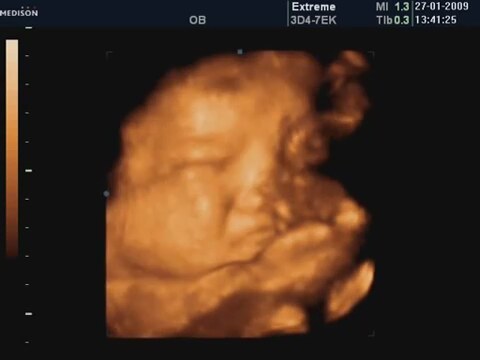

35 Haftalık Bebeğin 4 Boyutlu Ultrason Görüntüsü